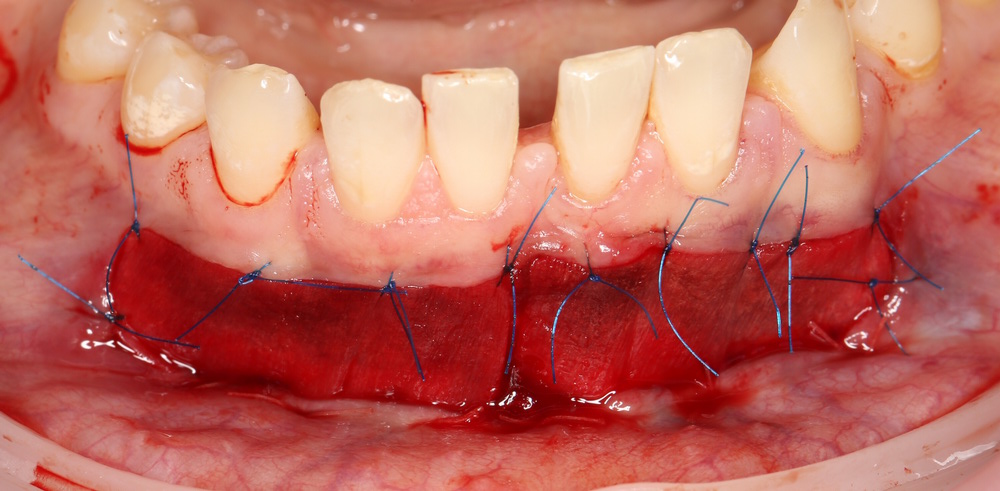

Матрица Mucograft имеет два слоя: наружный плотный и внутренний более рыхлый. Так вот, материал фиксируется швами за наружный плотный слой. В данном случае, я использовал нерезорбируемый шовный материал Prolene 6-0 в верхнем участке раны и Vicrlyl 6-0 — в нижнем:

Вообще, лучше везде фиксировать нерезорбируемым шовным материалом. Просто снятие швов в области будущей переходной складки представляет известные сложности (врастают), и я решил облегчить жизнь пациентке и себе. Но делать так постоянно не рекомендую — использование резорбируемых плетеных шовных материалов, особенно в условиях некачественной гигиены, может привести к образованию лигатурных свищей.

Матрица фиксируется, в первую очередь, к надкостнице, потом тем же вколом подцепляется слизистая оболочка. Получаются вот такие стежки:

Это как раз тот наглядный пример, где показана вся суть хирургии — мы больше шьем, чем режем.))

Операция закончена: